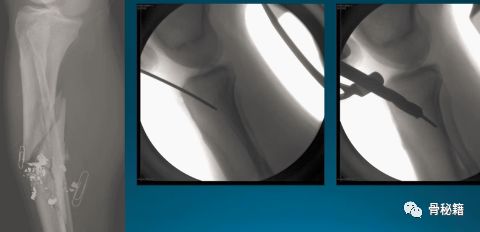

这样的骨折肯定长不上了,病人看了估计都会天天找你吧?翻修,近端加阻挡钉,小钢板